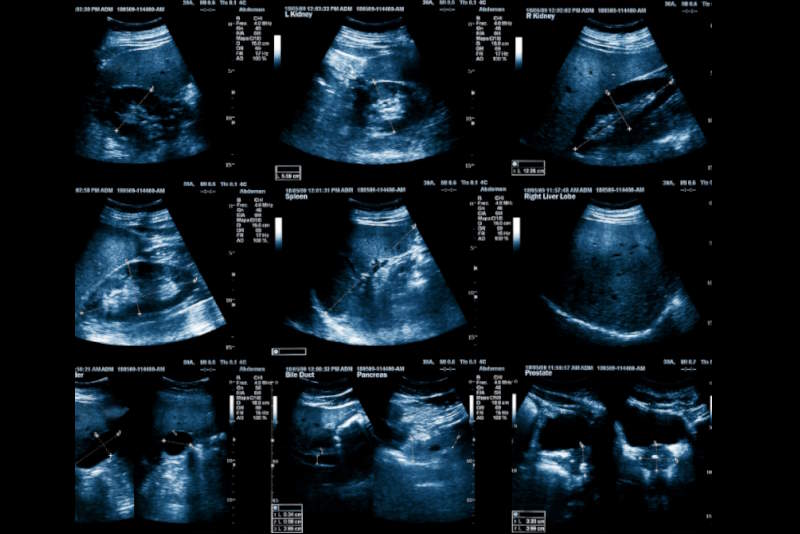

Durante l’esame, il medico applicherà un gel sull’addome e utilizzerà la sonda ecografica per ottenere immagini dettagliate. L’esame è indolore, dura generalmente 15-20 minuti e non richiede tempi di recupero. Il medico potrà chiedere respiri profondi per abbassare il diaframma e portare i reni più in basso, al di fuori dello scudo costale.